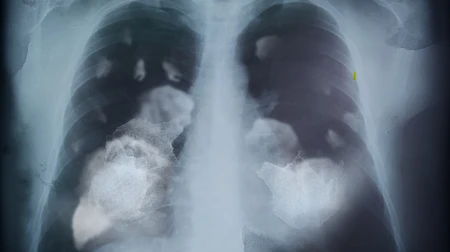

Lungenkrebs

Lungenkrebs gehört zu den gefährlichsten Krebsarten. Jedes Jahr erkranken in Deutschland über 50.000 Menschen neu daran. Das Heimtückische: Lungenkrebs macht lange keine Beschwerden. Viele erfahren erst von ihrer Erkrankung, wenn der Tumor bereits weit fortgeschritten ist und die Heilungschancen dann gering sind. Umso wichtiger ist es, die Krankheit frühzeitig zu entdecken. Die Radiologie spielt dabei eine Schlüsselrolle.